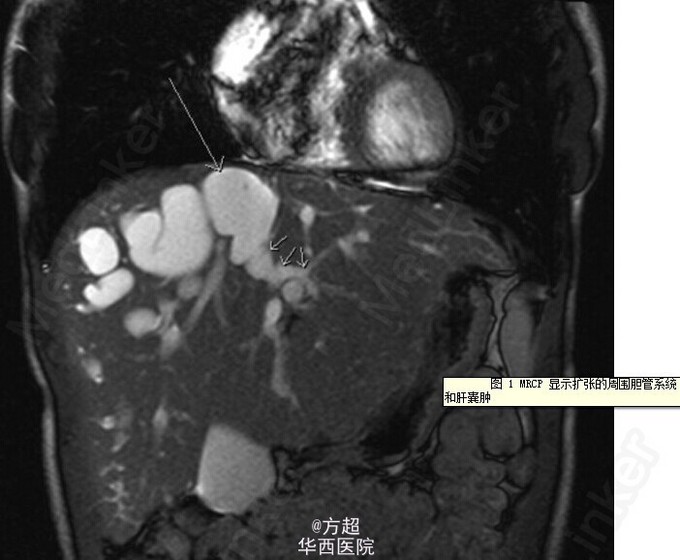

青年男性,因右上腹痛 4 周就诊,伴嗜睡、发热、盗汗、厌食及体重下降,既往有乳糜泻及肝囊肿病史,查体:T 38.2℃,肝脾巨大;血液化验结果提示胆红素 16umol/l、谷丙转氨酶 28IU/L、白蛋白 48g/L、国际标准化比率 1.05,均在正常范围,白细胞 14×109、C 反应蛋白 199mg/L、谷氨酰转肽酶 205 IU/L、碱性磷酸酶 274IU/L,较正常值升高;肝脏 B 超未见异常;进行了全面的败血症筛查之后,开始给予经验性应用广谱抗生素。全腹 CT 及 MRCP显示胆管系统明显的不规则的囊状扩张及巨脾,提示 Caroli 病合并门脉高压。经过抗感染治疗后症状好转离院。该病为常染色体阴性遗传,临床表现取决于发病年龄及是否存在肝脏、肾脏损害;易引起胆汁淤滞及胆管内结石等,该病引起终末期肝病及相关并发症的患者,可考虑施行肝移植。Cheung VTF, Joshi D, Amin Z, et al. Gut Published Online First;doi:10.1136/gutjnl-2014-306987